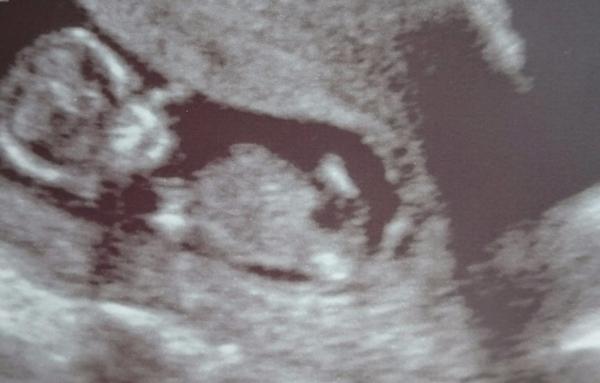

Je to holčička nebo chlapeček? Foto ultrazvuku

Ahoj maminky,mam tady foto z utz ve 20tt. Co myslite,holka nebo kluk? 🙂 Ja svuj tip mam a zajima me nazor nekoho jineho 🙂